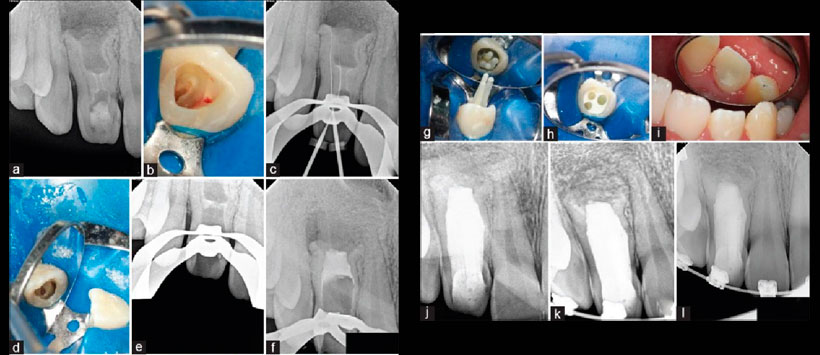

Figura 1: Tratamiento de la pieza 1.2. a) fotografía preoperatoria, b) Radiografía periapical preoperatoria, c) Tomografía computarizada cone beam en vista sagital muestra una completa comunicación entre la invaginación y el tejido periodontal, d) Tomografía computarizada cone beam en vista axial a nivel apical, se puede observar el sistema de la pulpa estrecha en forma de anillo adyacente al tejido de esmalte delimitando la invaginación por esmalte, e) forámen de la invaginación a nivel palatino, f) determinación de la longitud de trabajo, g) acceso conservador para evitar violar el espacio pulpar principal., h) obturación del conducto radicular con MTA, i) radiografía post-operatoria, j) control post endodoncia a los 19 meses.